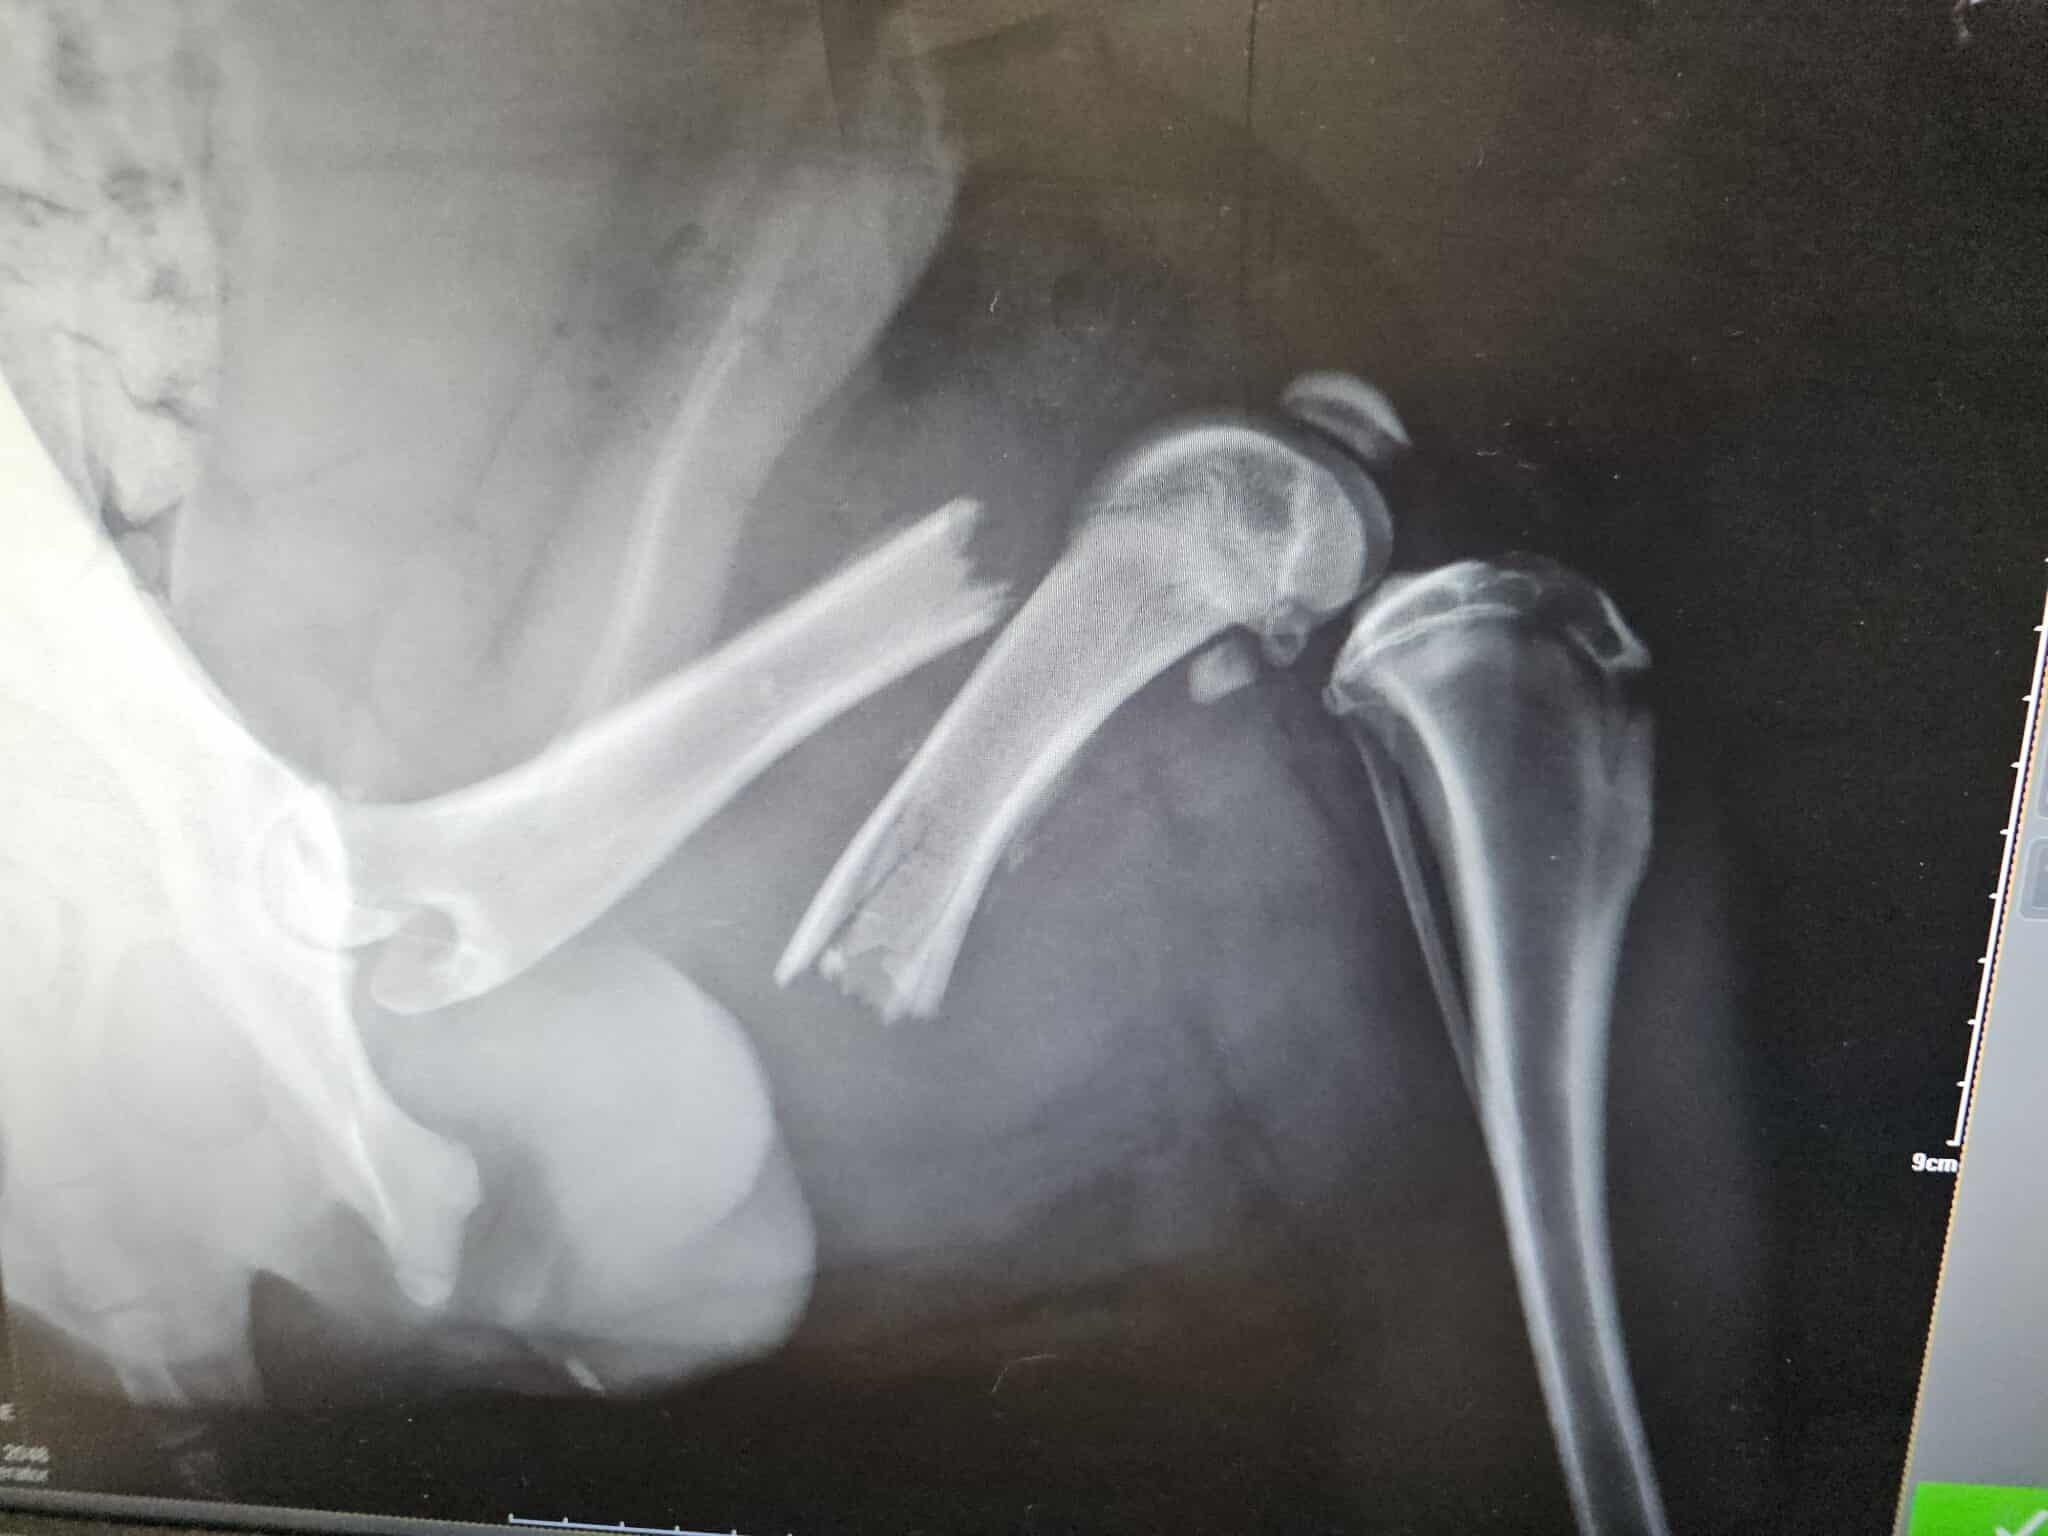

Conduit d’urgence chez le vétérinaire, le diagnostic est tombé : Lupi souffre d’une fracture du fémur et d’une fracture de la tête qui nécessite une prise en charge immédiate.